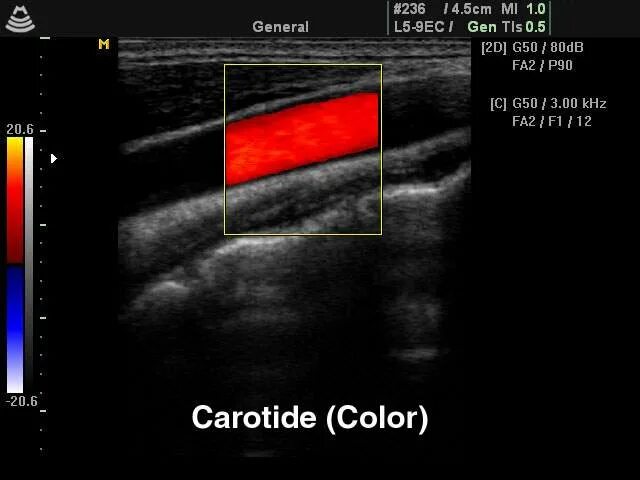

Сделать узи сонной артерии